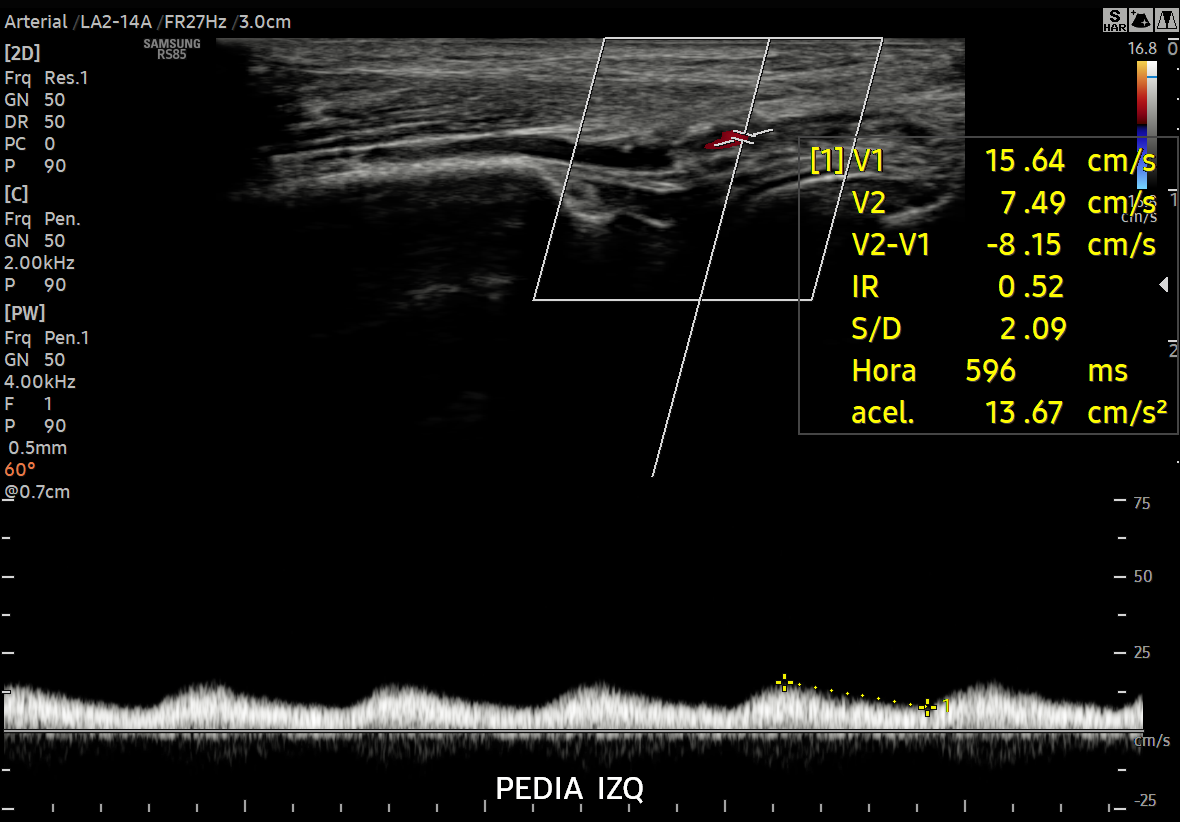

La ecografía Doppler arterial en Lima de segunda opinión es un estudio especializado dirigido a pacientes y médicos que requieren una reevaluación precisa del flujo arterial ante diagnósticos dudosos o hallazgos no concluyentes. En Diagnoimagen – Dr. Hubertino Díaz, aplicamos un enfoque avanzado que integra modo B, Doppler color y Doppler espectral, permitiendo un análisis completo de la hemodinámica arterial.

• Velocidades de flujo (PSV, EDV).

CASO REAL: INSUFICIENCIA ARTERIAL

ECOGRAFÍAS DE 2DA OPINIÓN ARTERIAL